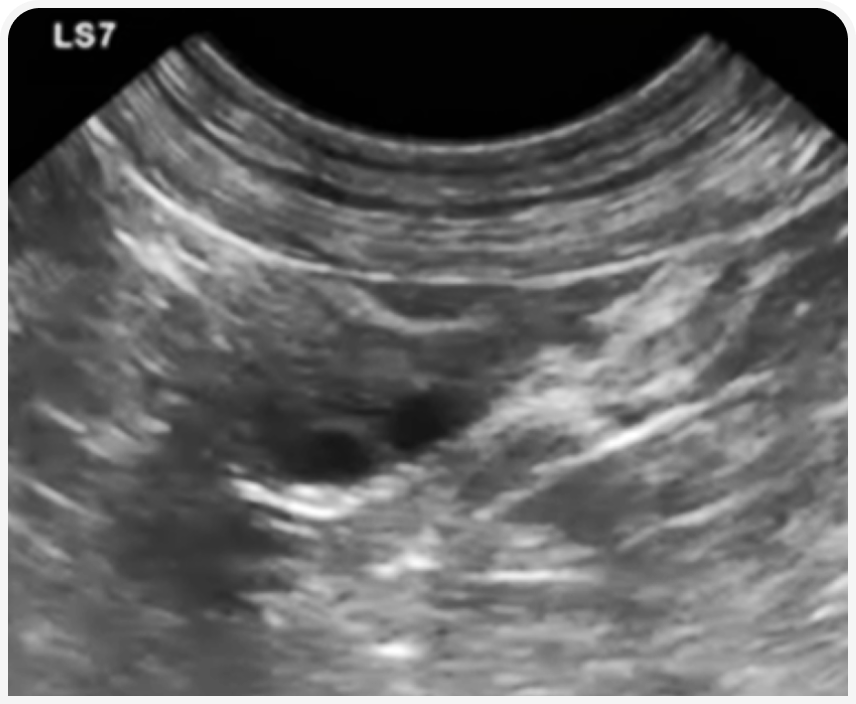

У некоторых животных в реминантном яичнике могут формироваться кисты, вызывающие персистентную течку. Тогда на УЗИ будут обнаружены единичная/множественные кистозные структуры, поликистоз или киста на фоне роста более мелких фолликулов.

У некоторых животных в реминантном яичнике могут формироваться кисты, вызывающие персистентную течку. Тогда на УЗИ будут обнаружены единичная/множественные кистозные структуры, поликистоз или киста на фоне роста более мелких фолликулов. В начале течки яичники могут не иметь хорошо различимых фолликулов. В таком случае стоит повторить исследование через неделю.

УЗИ у кошек с подозрением на ОРС часто затруднительно по причине меньшего размера и необходимости использовать высокочастотные трансдукторы.

Но, как и у сук, в течку яичники будут иметь характерную картину овального образования с множеством кистозных структур размером до 3-4 мм, а культя матки будет утолщаться. Алгоритм проведения исследования аналогичен алгоритму у сук.

Если при обследовании ветеринарный специалист не может обнаружить реминант на УЗИ, АМГ низкий, кошка старше 6 лет и от момента ОГЭ/ОЭ прошло более двух лет, в план обследования необходимо включить УЗИ брюшной полости с исследованием надпочечников. У собак на данный момент подобных случаев не зарегистрировано.